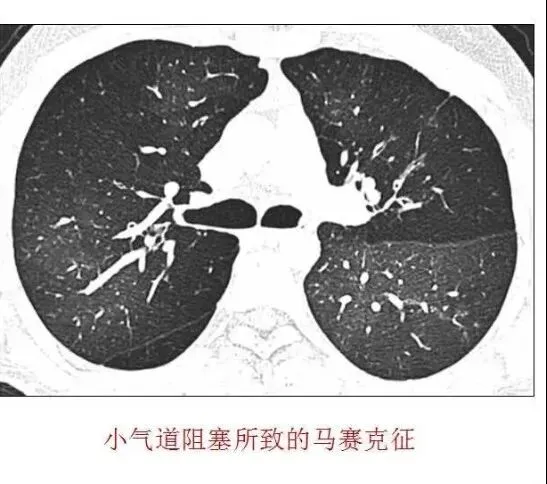

肺小气道病变主要累及直径<3mm 的细支气管,可以仅发生在小气道本身,也可是肺和大气道病变的延伸。“马赛克”衰减其形成主要是由于局部通气/血流分布差异所致。小气道病变时小气道管壁增厚、管腔阻塞,导致局部缺氧,造成反应性血管收缩,使受累肺实质密度减低;同时,管腔阻塞使阻塞局部出现局限性气体滞留,使局部肺血流再分布,正常肺实质血流量增多,导致正常肺实质密度增高,从而使肺实质的密度象“马赛克”一样黑白相间,形成“马赛克”衰减征象。

(1)气道性疾病:在气道性疾病中马赛克征的出现是由于呈补丁样分布的狭窄性毛细支气管炎和增殖性毛细支气管炎的病理改变造成局部缺氧血管痉挛,使局部血流灌注减少而形成的斑片样分布的气体潴留征象,影像表现为透亮度增高。即需要明确的是:从HRCT上看,病变区域是透亮度增高的区域,而不是透亮度降低的区域。以肺透亮度增高为异常表现,边缘清晰,血管管径缩小,呼气相可见空气潴留。